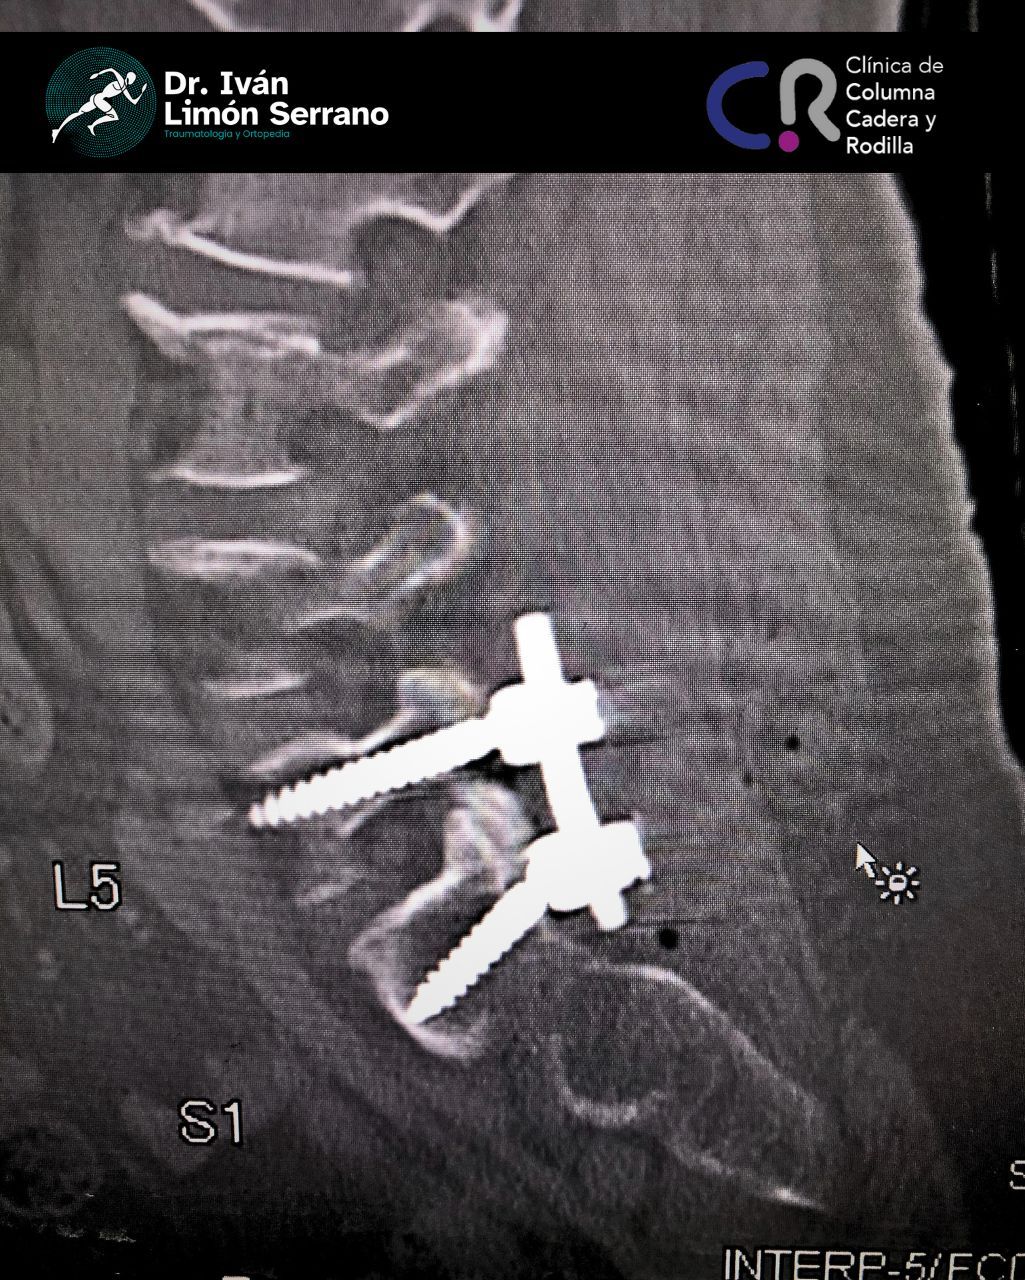

• Cirugía de columna

• Cirugía columna

Hernia de disco

Es una lesión que afecta a las estructuras de la columna vertebral, específicamente discos intervertebrales los cuales son estructuras blandas de consistencia gelatinosa cuya función es actuar como un amortiguador que absorbe el impacto y permite el movimiento de las vértebras. En ocasiones como ocurre durante los esfuerzos y los movimientos bruscos el disco se somete a una gran presión con lo que su anillo fibroso se desgarra, bien sea parcial o totalmente; este desgarro origina un trayecto por donde el material gelatinoso sale de su sitio originándose una hernia discal.